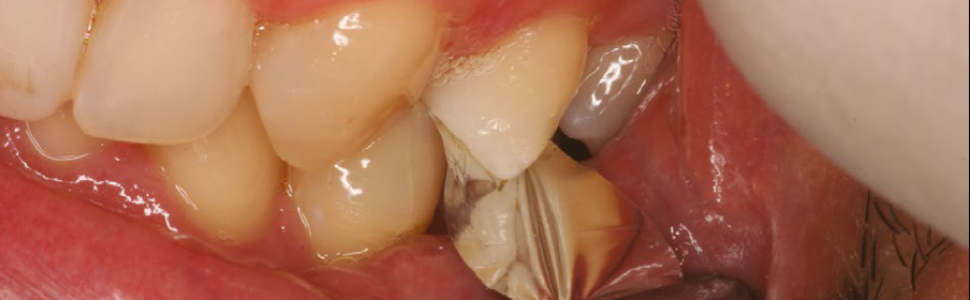

Starcie zębów (tooth wear – TW) może być klasyfikowane na wiele różnych sposobów: miejscowe, uogólnione, zębów przednich, zębów tylnych, zębów dolnych lub zębów górnych. Chociaż znaczna część przypadków patologicznego TW może być skutecznie leczona z zastosowaniem podejścia pasywno-profilaktycznego, u niektórych pacjentów wskazana będzie aktywna interwencja odtwórcza, na przykład w przypadku, gdy występują: